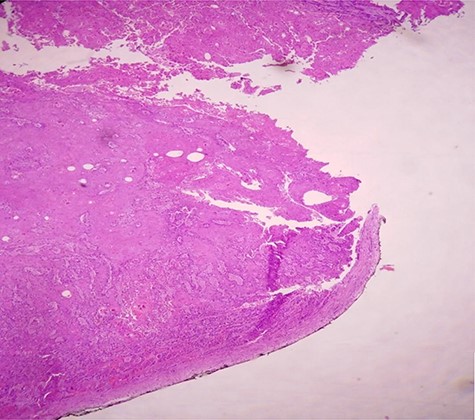

Postoperative course was marked by an aggravation of the septic shock, multiorgan failure, and death of the patient at Day 2 after surgery. Pathological examination concluded a pure SCC that massively invades the bladder muscle and perivesical fat (Figs 4–6).

H & E staining viewed under x10 with Olympus CX23 showing bladder wall infiltration with a SCC perforating serosa (bladder surface inked).